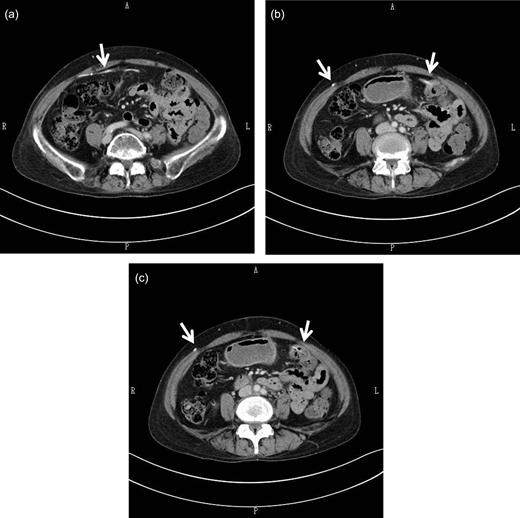

Abdominal CT scan findings. The shunt catheter (white arrow) extended through the right-rectus sheath (a), crossed the midline to the left side of the abdomen (a, b) and was inside the splenic flexure of the colon (b, c). There was no free air or other abnormalities in the abdominal cavity.